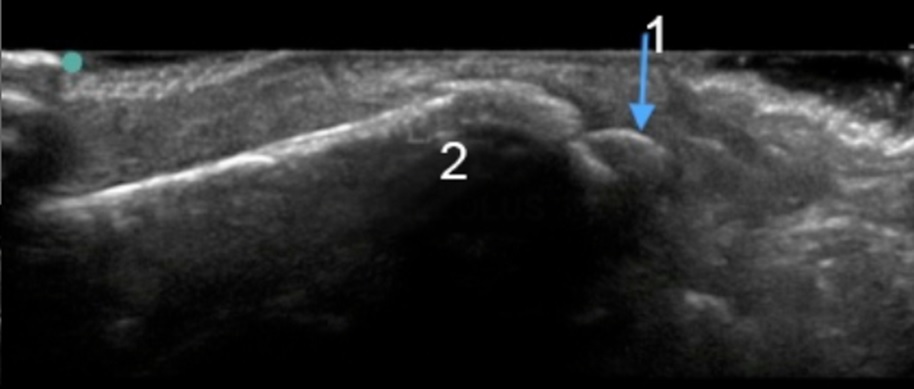

Bild: Fuß und Sprunggelenk, Abrissfraktur d. Malleolus lateralis

1. Abrissfraktur d. Malleolus lateralis

2. Malleolus lateralis